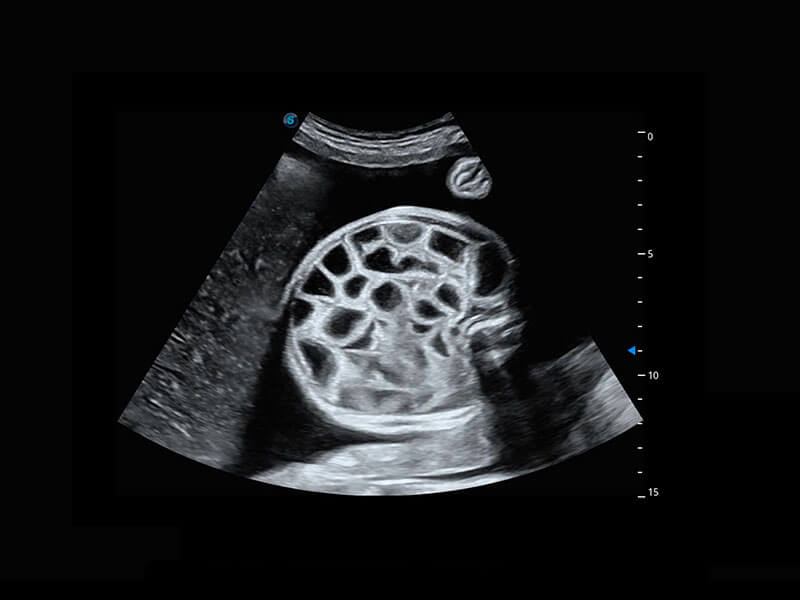

四腔切面